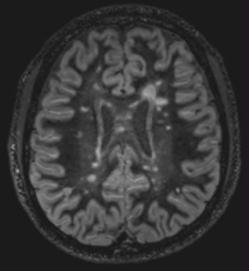

"Imagerie de la sclérose en plaques: où en sommes-nous en 2015?"

Samedi 21 mars 2015 - 9h-13h

Auditoire Mathias Mayor, CHUV, Lausanne

Dr Patric HAGMANN

- Programme (pdf)

- Syllabus du cours (pdf)